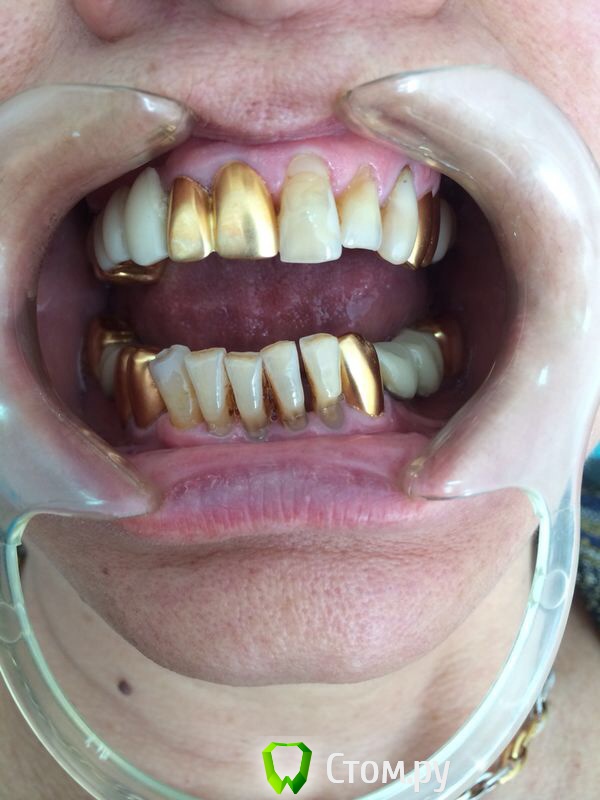

Ислам07 Опубликовано 18 мая, 2014 Поделиться Опубликовано 18 мая, 2014 Уважаемые коллеги подскажите пожалуйста план лечения, меня смущают клиновидные дефекты. Заранее спасибо Ссылка на комментарий

Ислам07 Опубликовано 18 мая, 2014 Автор Поделиться Опубликовано 18 мая, 2014 Не съемное. мне низ совсем не нравиться Ссылка на комментарий

Ислам07 Опубликовано 19 мая, 2014 Автор Поделиться Опубликовано 19 мая, 2014 В принципе она согласна на имплантацию, что с резцами делать????? Ссылка на комментарий

chernov Опубликовано 19 мая, 2014 Поделиться Опубликовано 19 мая, 2014 В принципе она согласна на имплантацию, что с резцами делать?????разгрузив(симплантировав),что угодно-коронки,виниры.......выбор за вами с пациентом Ссылка на комментарий